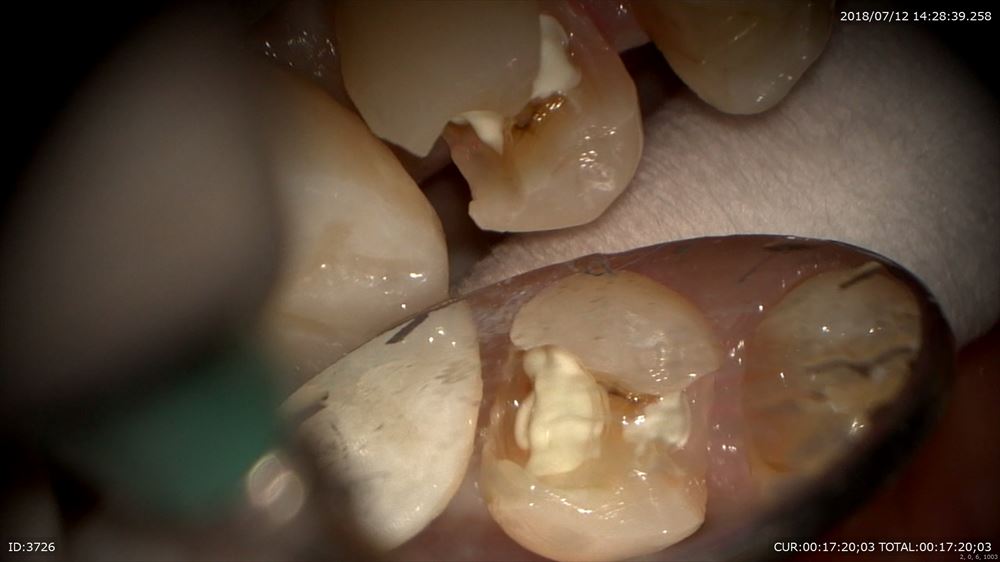

歯科ドックで左下の根管治療の不備とその手前に通常のレントゲンには映りにくい場所の虫歯をCTで発見しました。

ほらCTとマイクロスコープを使用すると。。

CTにはしっかり写っていました。歯科ドックは大切。

神経に触れています。